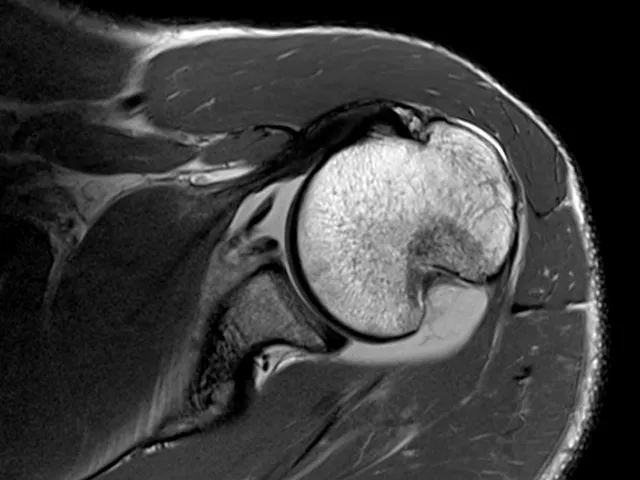

Radiologists who would like to become more confident with the interpretation of Imaging of Sport Injuries will find the fellowship useful.

This fellowship, which provides basic and early advanced knowledge, will give participants an overview of the common and less common presentation of Sports Injuries, as well as which imaging modality is best suited to image with, as well as to get to the correct diagnosis. Shoulder, elbow, wrist, pelvic and groin, knee, foot, ankle, and other injuries will be examined.

"I really liked the cases and the way they were presented, showing us a systematic approach to MRI report. Informative, practical, and very useful for practice."

Dr. Henry Bartlett, Radiologist, Mossel Bay Radiology (Fellow, Nov 2021)